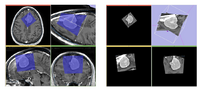

FastMarching segmentation module in Slicer 3.6: Segmentation of a meningioma

B-Spline Registration in Slicer 3.6 allows for non-rigid registration between pre-procedure MRI and intra-procedure CT images during CT guided tumor ablation in the liver. It provides increased tumor visualization during the planning, targeting and monitoring phases of the ablation procedure.

Planning for CT Radiosurgery augmented with diffusion tractography (fibers: internal capsule, corpus callosum and the environment of the tumor, which is a metastatic tumor in the parietal lobe) Image Courtesy of University of Debrecen, Medical School and Health Science Center more information...